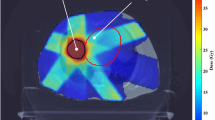

Our study is motivated by radiation therapy design for cancer treatment. We consider large-scale problems with stochastic order constraints. We establish a general result about the form of the deepest cuts associated with events of positive probability which are used in the numerical approximation of the functional constraints. An efficient method using the deepest cuts is proposed for the numerical solution of problems with second-order dominance constraints and increasing convex order constraints. We the propose a new methodology for the radiation-therapy design for cancer treatment. We introduce a risk-averse optimization problem with two types of stochastic order relations and with coherent measures of risk and consider the effect of the risk models in three versions of the problem formulation. Additionally, we propose a method that creates flexible (floating) benchmark distributions when benchmark distributions are not given apriori or when the provided distributions lead to infeasibility. We devise a numerical method using floating benchmarks for solving the proposed risk-averse optimization models for radiation therapy design. The models and methods are verified by using clinical data confirming the viability of the proposed methodology and its efficiency.

The authors express their gratitude to Dr. Ning J. Yue, Department of Radiation Oncology, The Rutgers University Robert–Wood–Johnson Medical School, for kindly providing us with clinical data for the experiments. We are also grateful to the three anonymous referees whose critics helped improve the paper.